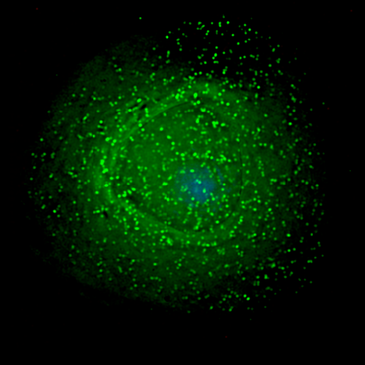

Sin embargo, el sistema inmunológico no conseguirá eliminar completamente el VIH. El virus se esconde, debilitando lentamente las defensas del organismo y destruyendo las células T CD4, que juegan un papel clave en la respuesta inmunológica. Si no se administra el tratamiento, el sistema inmunológico queda cada vez más comprometido exponiendo al individuo a un riesgo creciente de desarrollar otras infecciones que podrían amenazar su vida.

Para evitar este extremo, las guías internacionales de tratamiento recomiendan que cuando el número de células T CD4 disminuye hasta cierto nivel – 350 células por milímetro cúbico – los individuos empiecen un tratamiento de por vida con fármacos antirretrovirales. Estos medicamentos no sólo evitan que se siga destruyendo el sistema inmunológico, sino que posibilitan su recuperación.